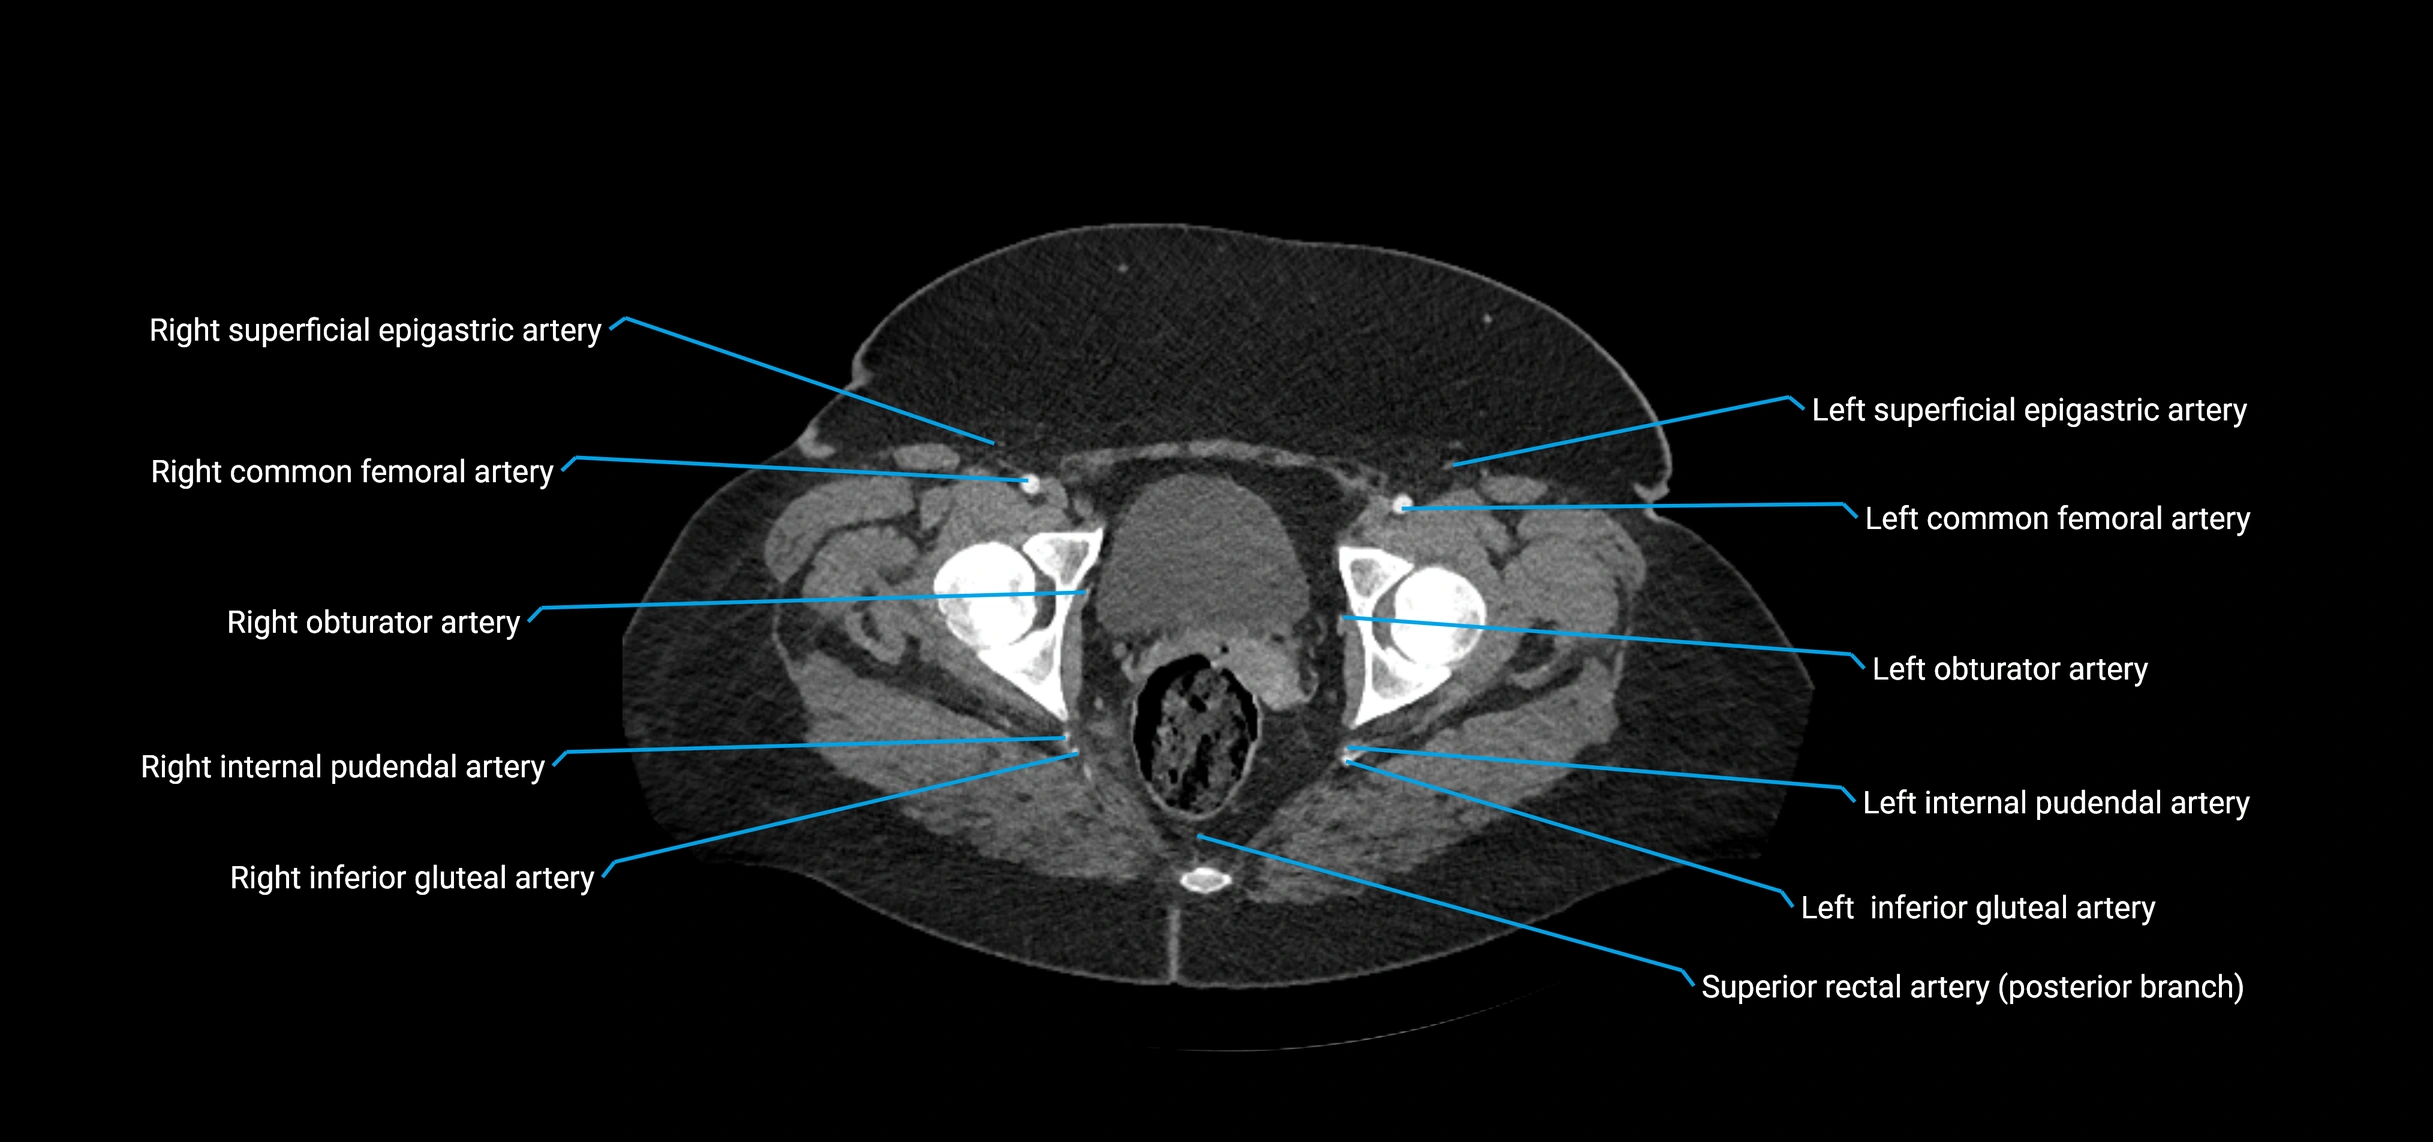

Contrast-enhanced CT (CTA):

• Gold standard for abdominal aortic imaging

• Provides excellent detail of lumen, wall, aneurysm, thrombus, and branch vessels

• Multiplanar and 3D reconstructions help in aneurysm measurement, stent graft planning, and dissection evaluation